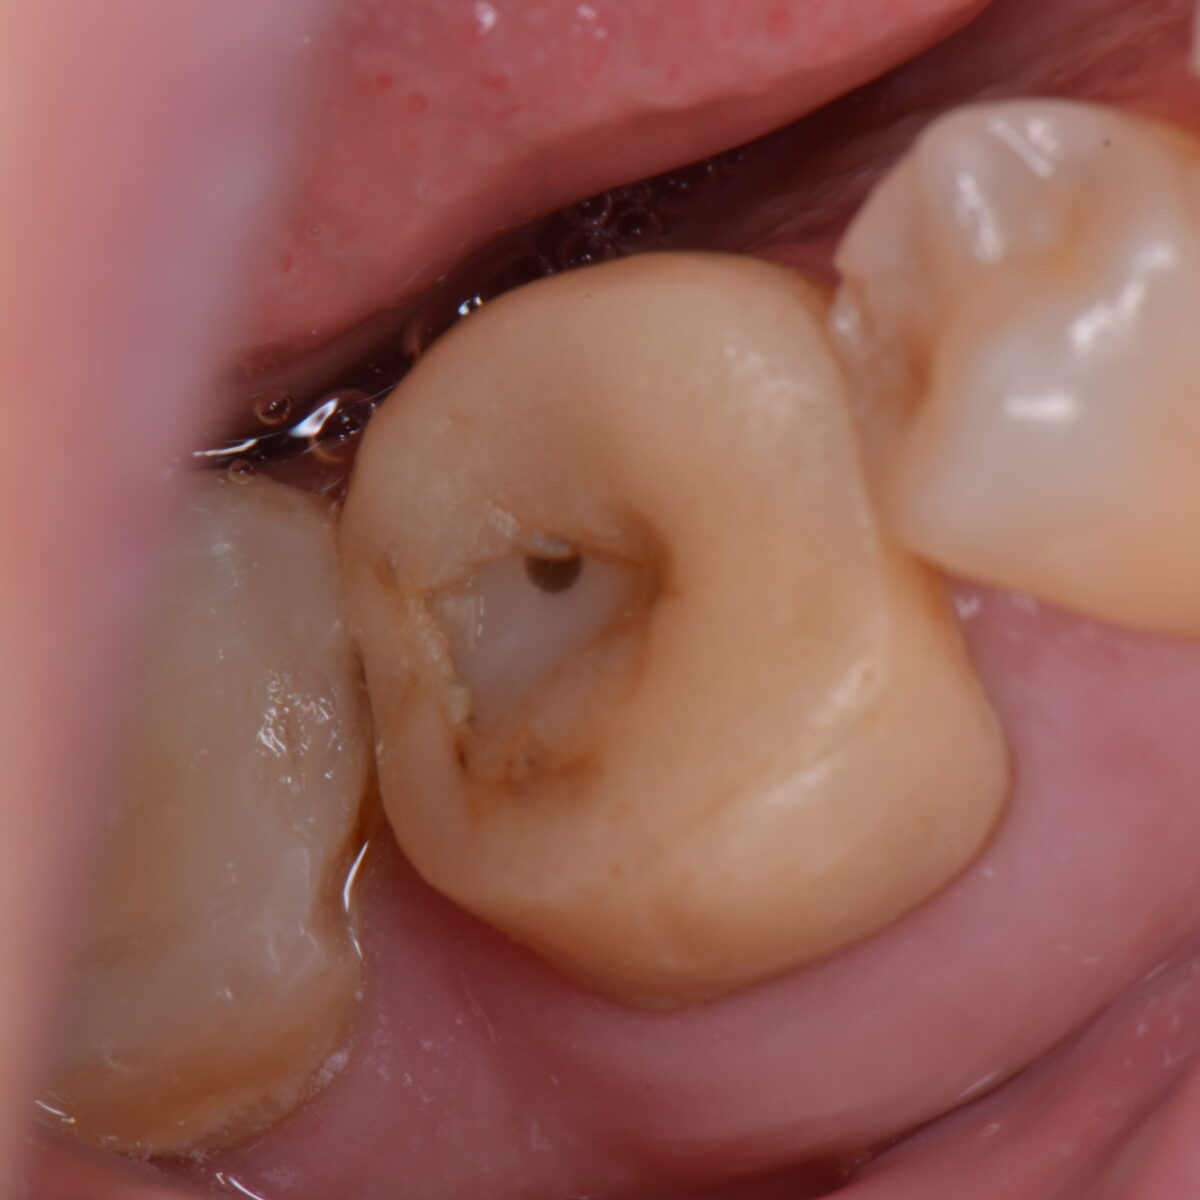

銀歯の下には・・・

【東京メトロ東西線妙典駅 徒歩5分の歯医者】市川、妙典の歯科医院、めぐりデンタルクリニックの梶原です。 今日は、銀歯の下がどうなっているかを載せます。 こちらにも同様のことを書いて…